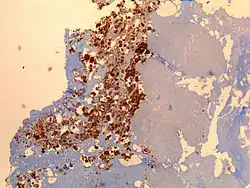

![]() | |

| Immunohistochemical detection of C. burnetii in resected cardiac valve of a 60-year-old man with Q fever endocarditis, Cayenne, French Guiana: Monoclonal antibodies against C. burnetii and hematoxylin were used for staining; original magnification is ×50. | |